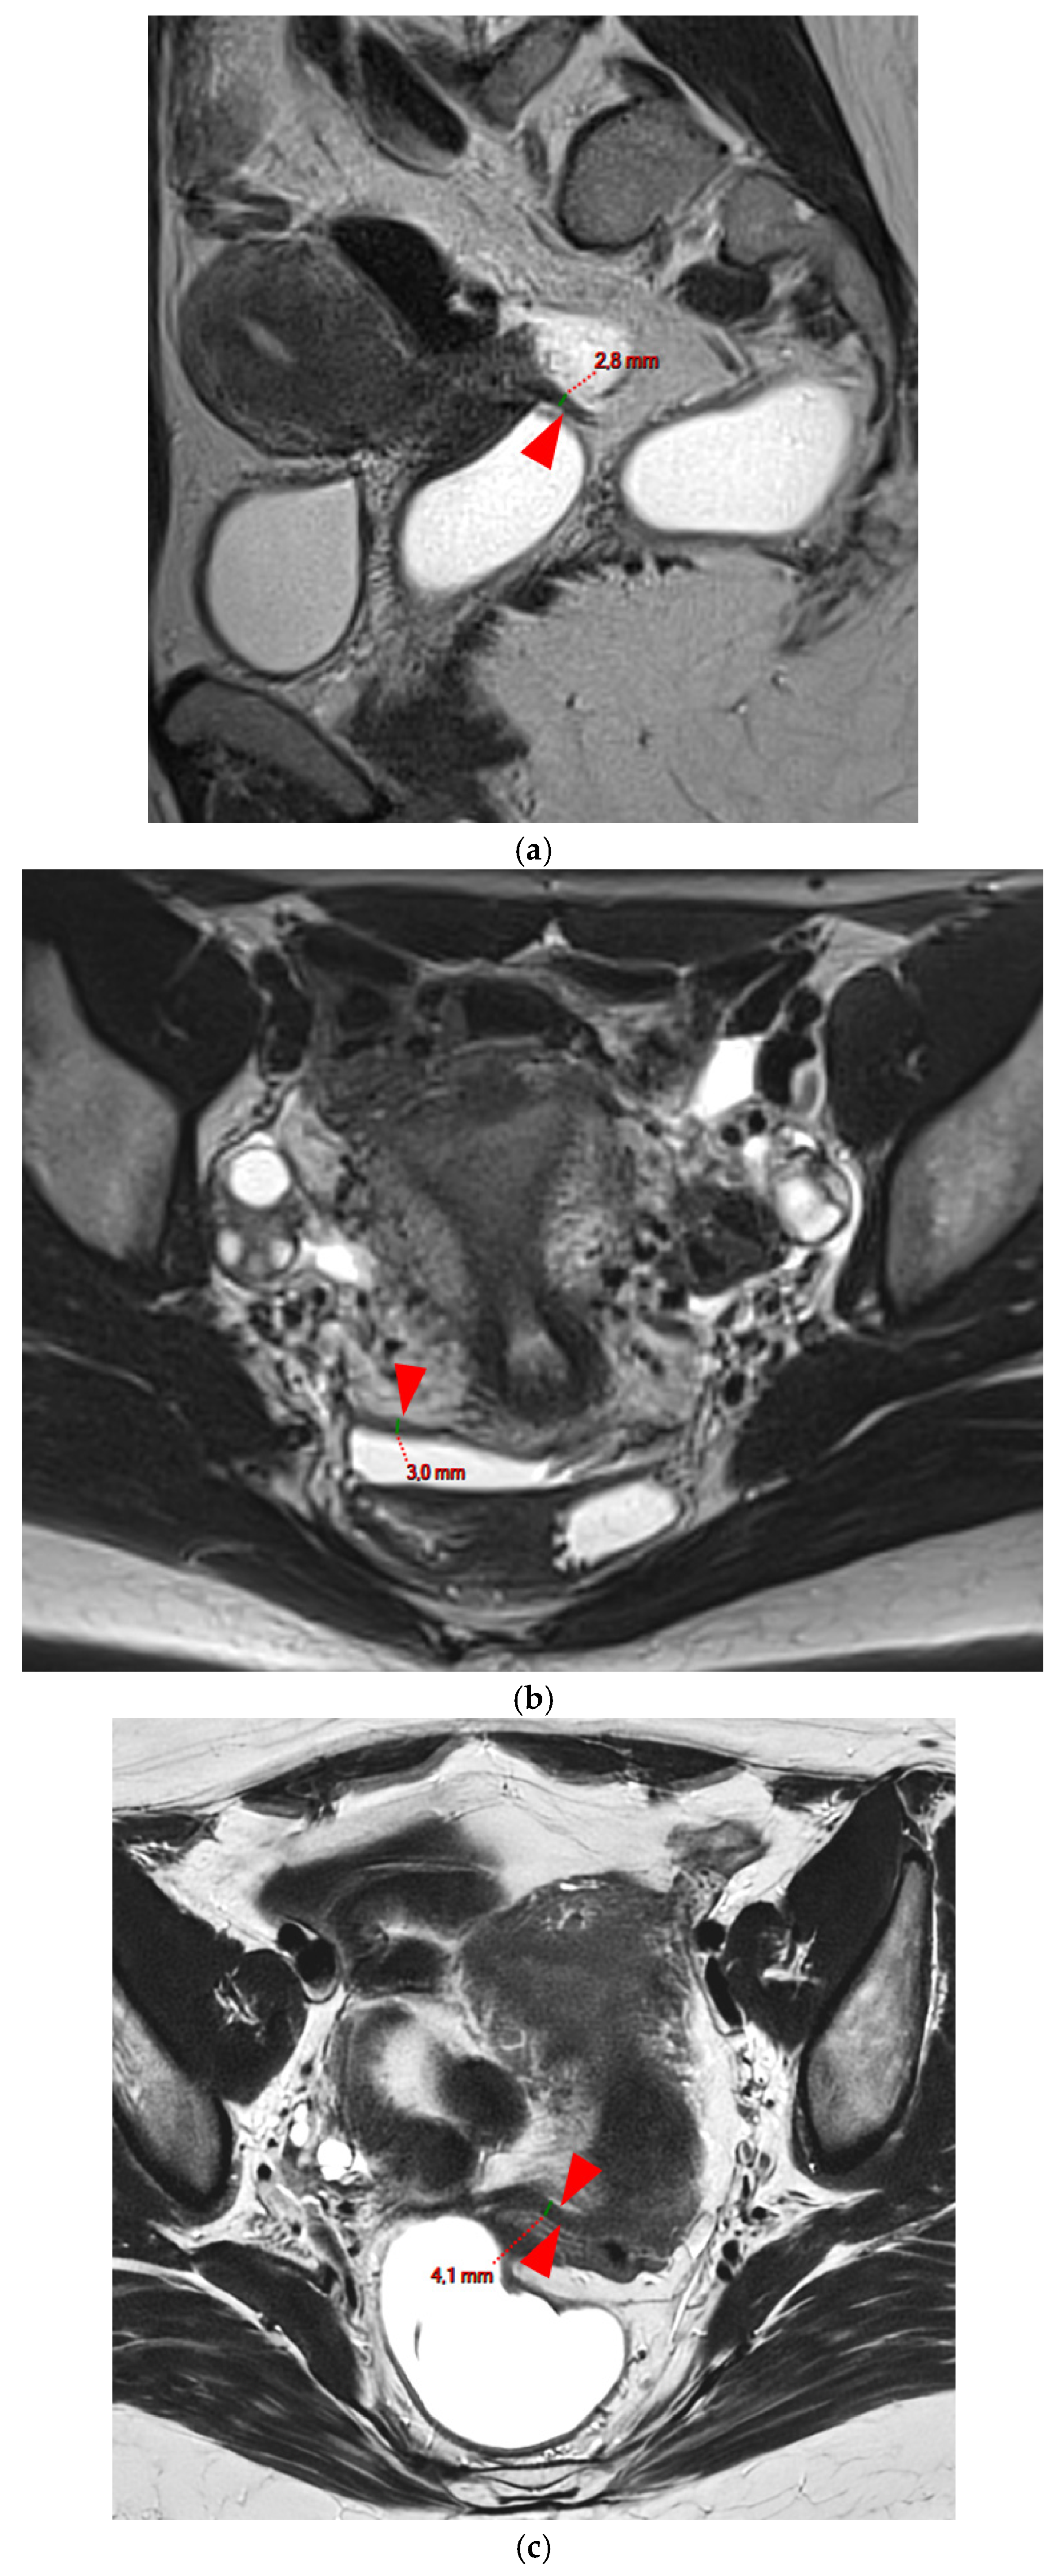

Figure 3. Pelvic MRI scans of three patients with thick (>2 mm), smooth, and regular USLs (HTD type 3A). (a) Sagittal T2WI: a thick (2.8 mm), smooth, tapering-shaped left USL (arrowhead). (b) Axial T2WI: regularly thickened (3 mm) right USL with a smooth surface (arrowhead). (c) Axial T2WI: regularly thickened (4.1 mm) right USL with a smooth surface (arrowheads).

A type 3 USL appears as thickened (i.e., >2 mm), and can be classified either as type 3A (PPV = 75%; FPR = 25%) or as type 3B (PPV = 80%; FPR = 20%).

A type 3A USL (Figure 3) maintains a smooth appearance with regular margins and often retains a tapering shape despite its thickening.